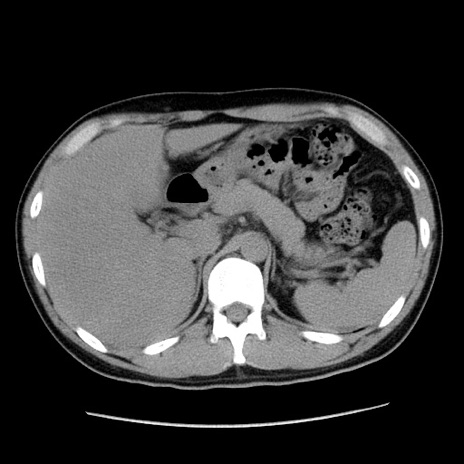

症例36(横断像)

【症例】20歳代 男性

【主訴】心窩部痛

【現病歴】今朝より上腹部痛あり。一旦軽快していたが再度出現したため救急要請。昨日夕に白身の魚を含む刺身を食べた。

【身体所見】BP 136/89mmHg、HR 74/min、BT 37.0℃、腹部:膨満、軟、心窩部に圧痛あり。反跳痛なし、筋性防御なし、腸雑音やや亢進あり。

【データ】WBC 17700、CRP 0.48